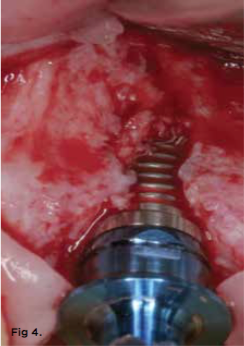

Typically, bone is cut prior to implant placement with the use of standard drill burs. While drill bits rotate, the cutting resistance vector has been described as "constantly changing," and this can cause the drill bit to shave along the bone surface away from the initial osteotomy site, inducing less-than-optimal site preparations (Figure 2 through Figure 4).37 Since fresh, hydrated trabecular bone is a ductile material, it has a good capacity for plastic deformation. Osseodensification is essentially a burnishing process that redistributes bone material on the bony surface through plastic deformation.37 The counterclockwise rotation of osseodensification burs causes the lands of the bur to slide across the surface of the bone by means of low plastic deformation that is purposefully designed to have a compressive force less than the ultimate strength of the bone.

Fig 3. Implant placement using standard burs may potentially lead to off-axis drilling, which at times may compromise implant outcomes or long-term esthetic results. These three photographs show examples of cases in which multiple implant threads were left exposed due to thin buccal bone relative to the implant placement (clinical photographs courtesy of Salah Huwais, DDS).

Figure 3